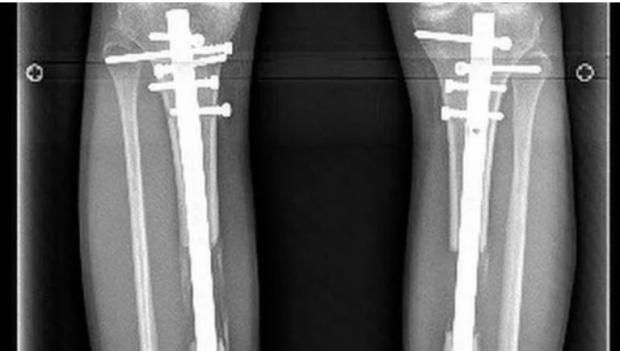

في واحدةٍ من أكثر الإصابات قسوة هذا الموسم، تعرض اللاعب الجزائري أحمد القندوسي، المعار من النادي الأهلي إلى سيراميكا كليوباترا، إلى كسرٍ مضاعف في الساق خلال مباراة أمام نادي فاركو، ليُصاب الذهول في المدرجات والصمت في المستطيل الأخضر، وكانت الإصابة عنيفة لدرجة أنها استدعت تدخلًا جراحيًا عاجلًا لتركيب مسمار نخاعي داخلي لتثبيت العظام، وهي من العمليات الدقيقة التي تُستخدم غالبًا في الحالات المعقّدة.

ونجحت العملية الجراحية التي خضع لها اللاعب، وتحتاج بعدها مرحلة دقيقة من التأهيل والعلاج الطبيعي، والتي تُعد حاسمة في تقرير مصير اللاعب وقدرته على العودة للملاعب بنفس القوة، وفي هذا السياق، كشف الدكتور أحمد علام، استشاري العلاج الطبيعي، في تصريحات خاصة لـ«الوطن»، تفاصيل المرحلة التي يعيشها اللاعب حاليًا، وخطوات التأهيل المنتظر اتباعها بدقة.

وأضاف علام أنّ التقييم المستمر باستخدام الأشعة هو الفيصل في تحديد مدى تقدم الالتئام، مشيرًا إلى أن أي استعجال في زيادة الأحمال قد يؤدي إلى مضاعفات خطيرة، أو تأخر التئام العظام، وهو ما يمثل كابوسًا لأي لاعب محترف.